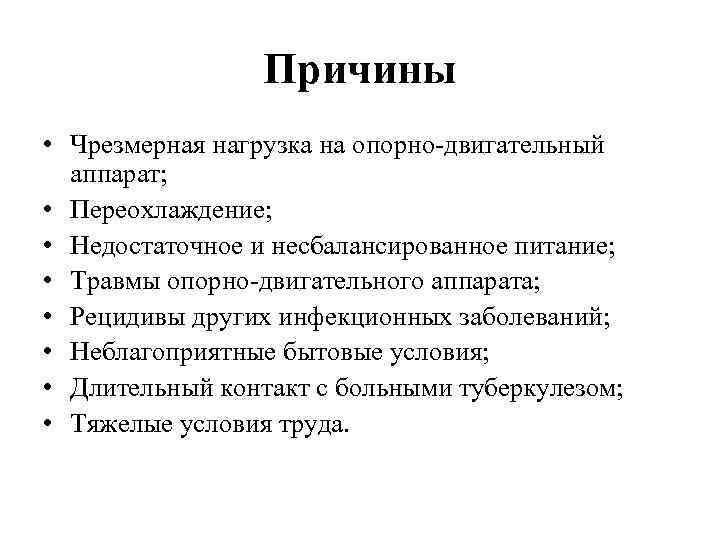

Причины • Чрезмерная нагрузка на опорно-двигательный аппарат; • Переохлаждение; • Недостаточное и несбалансированное питание; • Травмы опорно-двигательного аппарата; • Рецидивы других инфекционных заболеваний; • Неблагоприятные бытовые условия; • Длительный контакт с больными туберкулезом; • Тяжелые условия труда.

Причины • Чрезмерная нагрузка на опорно-двигательный аппарат; • Переохлаждение; • Недостаточное и несбалансированное питание; • Травмы опорно-двигательного аппарата; • Рецидивы других инфекционных заболеваний; • Неблагоприятные бытовые условия; • Длительный контакт с больными туберкулезом; • Тяжелые условия труда.